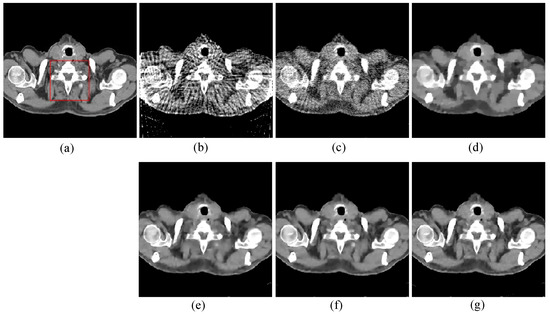

Figure 3. 64 views reconstruction results of pelvic image: (a) ground truth, (b) FBP, (c) OS-SART, (d) TV, (e) PICCS, (f) TVPI-G, and (g) NPICCS. The display window is [−150 250] HU.

The first image reconstruction experiment is using a pelvic image to show the feasibility of our algorithm for SVCT reconstruction, as shown in Figure 1. We extracted 80, 64, and 48 views from a full scan and selected parameters empirically. The parameters are set as follows: a = 0.5, γ1 = 0.3, and γ2 = 0.08. Figure 2, Figure 3 and Figure 4 show the ground truth and reconstruction images via FBP, OS-SART, TV, PICCS, TVPI-G, and our method NPICCS. From these figures, it is evident that our algorithm outperforms the other methods in terms of recovering image structures and suppressing noise. Specifically, the FBP and OS-SART results (as shown in Figure 2b,c, Figure 3b,c and Figure 4b,c) contain high levels of noise and artifacts, while TV results (as shown in Figure 2d, Figure 3d and Figure 4d) are characterized by blurring and staircasing effects. The PICCS and TVPI-G methods provide better results than the other approaches because of the introduction of prior information, but image edges are missing as shown in Figure 2e,f, Figure 3e,f and Figure 4e,f. At the same time, it can be seen that our method is able to preserve image edges and suppress noise effectively, as shown in Figure 2g, Figure 3g and Figure 4g.

To compare the recovery of reconstructed image details and edge information, we selected two regions of interest (ROIs) from the 48-view and 64-view reconstructed images and zoomed in to show. The ROIs are labelled with red box as shown in Figure 2a and Figure 3a. The corresponding zoomed-in results are shown in Figure 5. As can be seen from the figure, our algorithm can reconstruct some small image structures shown by the arrows, which are difficult to see by other algorithms. Also, we find that our algorithm performs better in edge retention.